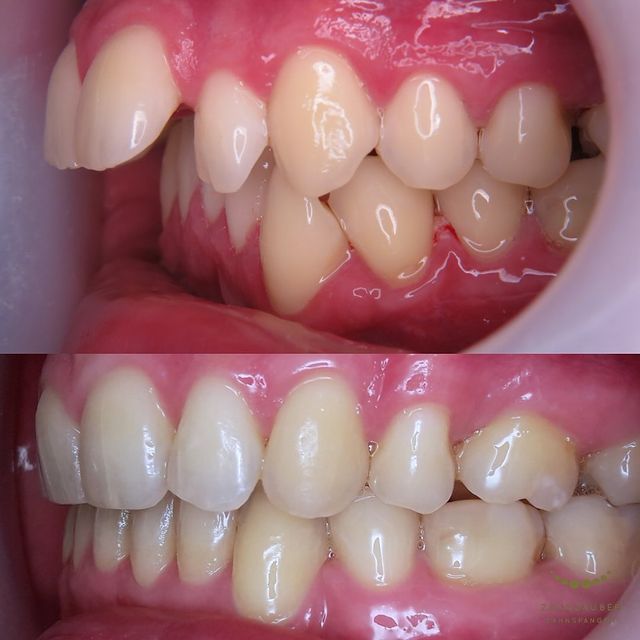

Vorher: Der Patient kam mit einer asymmetrischen Klasse-II-Malokklusion, einem Engstand und einem Vorbiss von 14 mm. Zusätzlich lag eine retrognathe Mandibula vor, was die Kieferstellung beeinträchtigte und funktionelle Probleme verursachte.

Nachher: Nach der zweijährigen Behandlung, in der vier Zähne entfernt und der Unterkiefer operativ korrigiert wurden, wurde ein dauerhafter Retainer eingesetzt, um die ideale Position der Zähne langfristig zu stabilisieren. Der Patient verließ die Praxis mit einem harmonisch ausgerichteten und funktional verbesserten Gebiss.